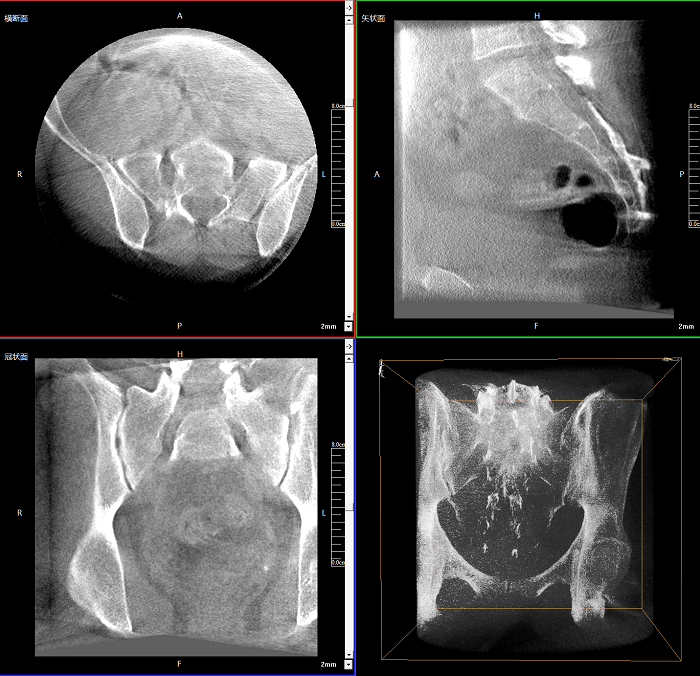

術(shù)中CT檢查 減少翻修概率

通過術(shù)中三維影像的檢查,可以立即發(fā)現(xiàn)植入物的錯(cuò)位,減少不必要的第二次手術(shù),減少并發(fā)癥概率以及感染風(fēng)險(xiǎn)。

Clinical picture

臨床圖片